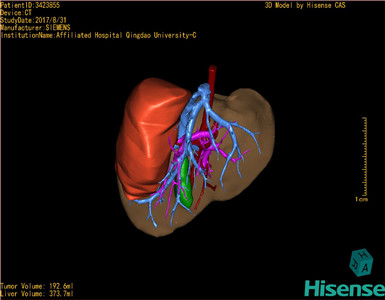

将0.625mm双源薄层CT资料的静脉期和动脉期Dicom格式文件导入海信CAS系统。

通过调节窗宽窗位调整CT序号,对肝实质,胆囊,下腔静脉,肿瘤,肝动脉、门静脉及肝静脉等进行三维重建;系统自动计算肝脏体积。

模拟手术操作,自动计算切除肿瘤体积。肝脏体积为373.7ml,肿瘤体积是192.6ml,是肝脏体积的0.5倍,通过比对2-3岁正常肝脏体积为475.97±99.7ml,通过术前模拟手术,精准判断切除后剩余肝脏体积能耐受,避免肝衰竭发生。

术前三维重建:

重建图片